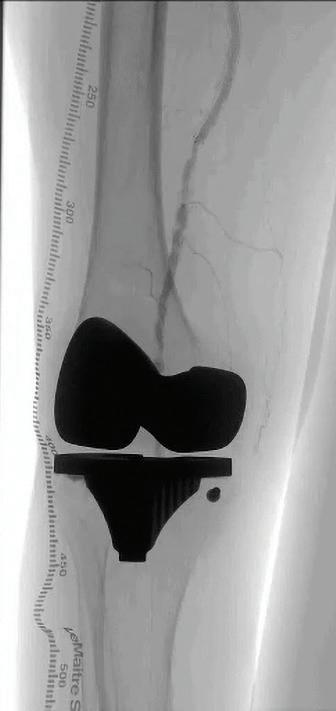

*All: drug, scaffold, resorbable excluding platinum markers.

1. Reintervention defined as CD-TLR. 2. Brian G. DeRubertis et al., Two-Year Outcomes of the LIFE-BTK Randomized Controlled Trial Evaluating the Esprit™ BTK Drug-eluting Resorbable Scaffold for Treatment of Infrapopliteal Lesions, VIVA 2024.

INDICATIONS The Esprit™ BTK Everolimus Eluting Resorbable Scaffold System is indicated for improving luminal diameter in infrapopliteal lesions in patients with chronic limb-threatening ischemia (CLTI) and total scaffolding length up to 170 mm with a reference vessel diameter of ≥ 2.5 mm and ≤ 4.00 mm.

MAT-2408411 v3.0 48% fewer patients require reinterventions through 2 years.1,2 Go above expectations with the only device that does it all for CLTI.*